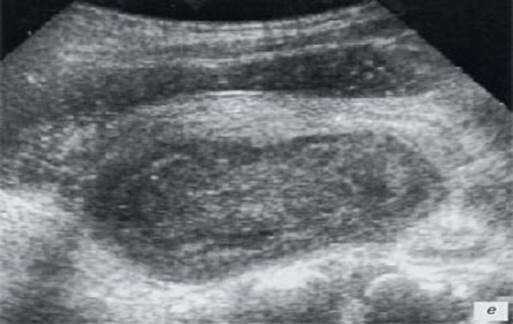

В диагностике аппендикулярного инфильтрата используют УЗИ, при выполнении которого в проекции аппендикулярного инфильтрата обнаруживаются неподвижные, ригидные, неправильной формы образования с недостаточно четкими границами, неоднородной эхоструктурой со скоплениями гипоэхогенной жидкости Толщина стенок вовлеченных в процесс петель кишечника превышает 3 мм. Перистальтика кишечника в зоне инфильтрата отсутствует. Червеобразный отросток визуализируется нечетко из-за деструктивных изменений в стенке самого отростка и инфильтрации в окружающих тканей. В дальнейшем УЗИ используется для определения динамики воспалительных изменений с течением времени и под влиянием проводимого лечения (рассасывание или абсцедирование), что позволяет уточнить лечебную тактику (Рис. 3).

Рисунок 3. Аппендикулярный инфильтрат при тазовом расположении отростка. УЗИ[3].